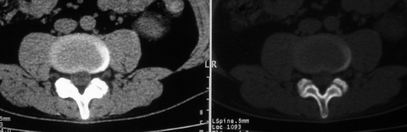

以下是引用余辉在2008-10-23 16:14:00的发言:[br]腰椎体棱角分明,小关节退变部分隔合,骶髂关节部分融合,考强脊炎